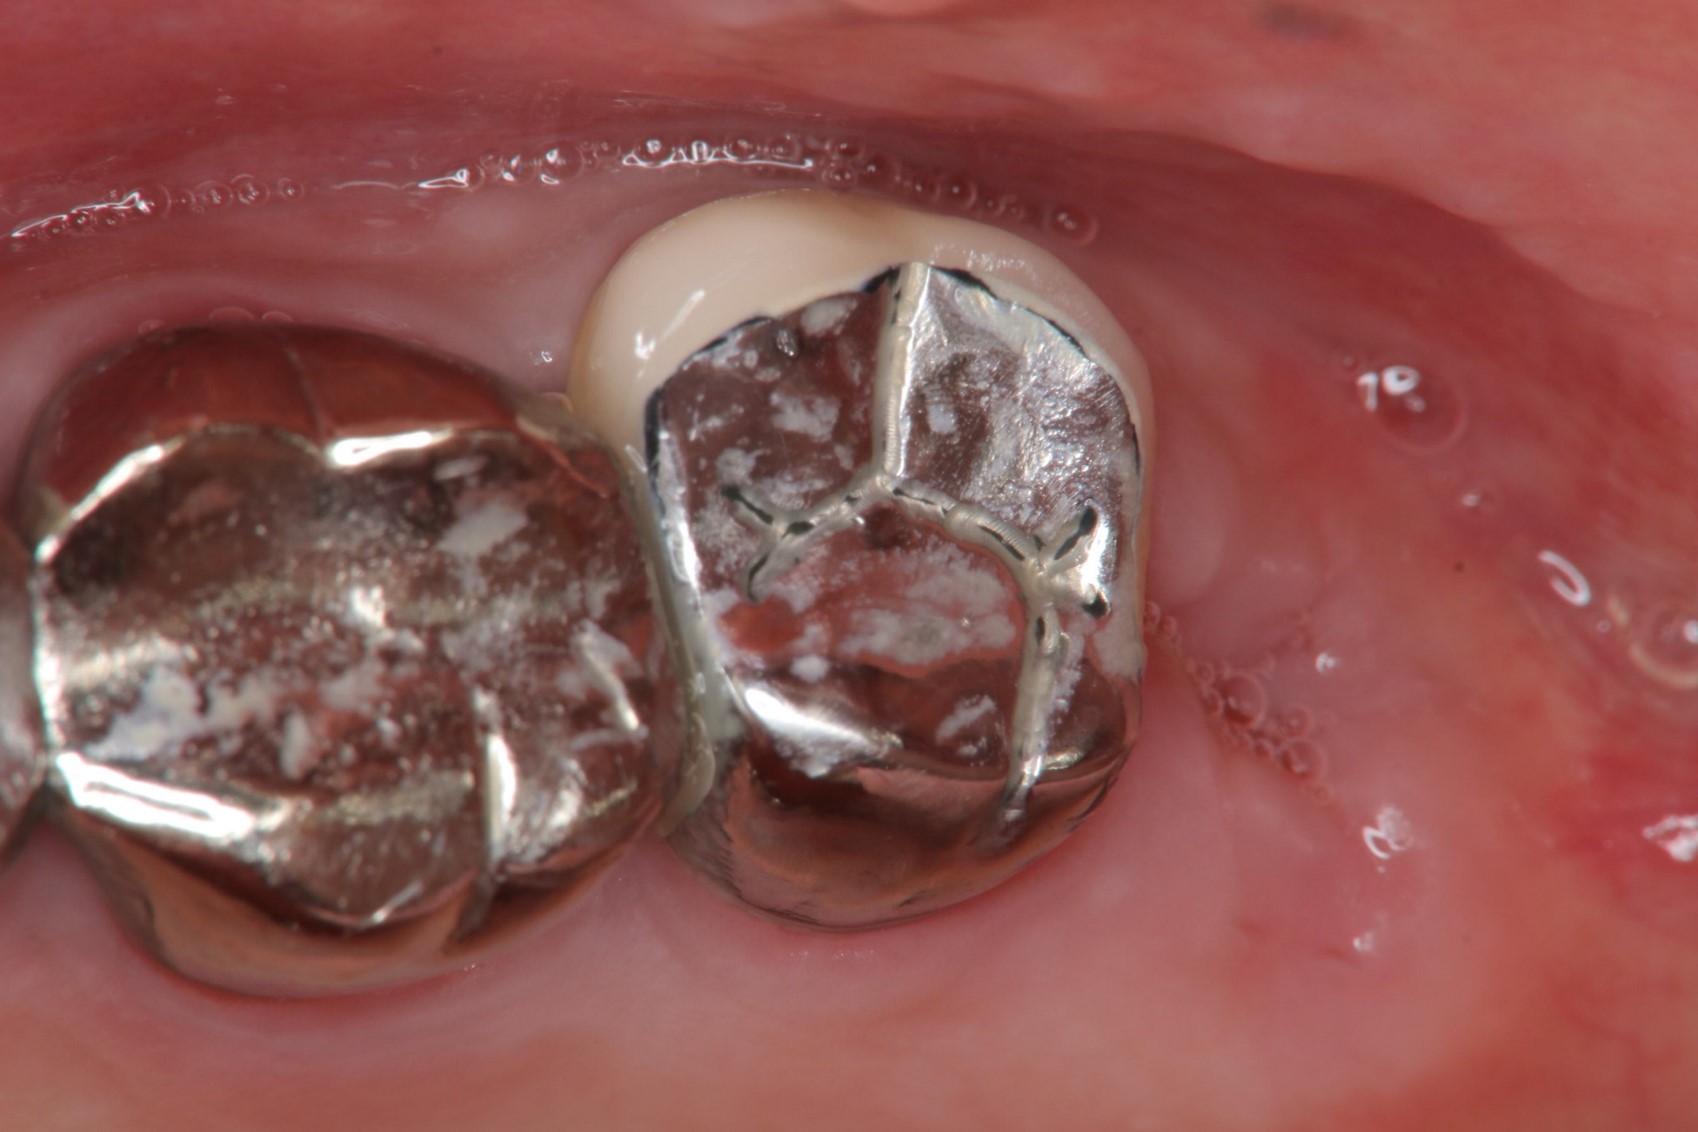

微創拔除阻生齒,骨膠原修復並縫合

1週後傷口癒合良好